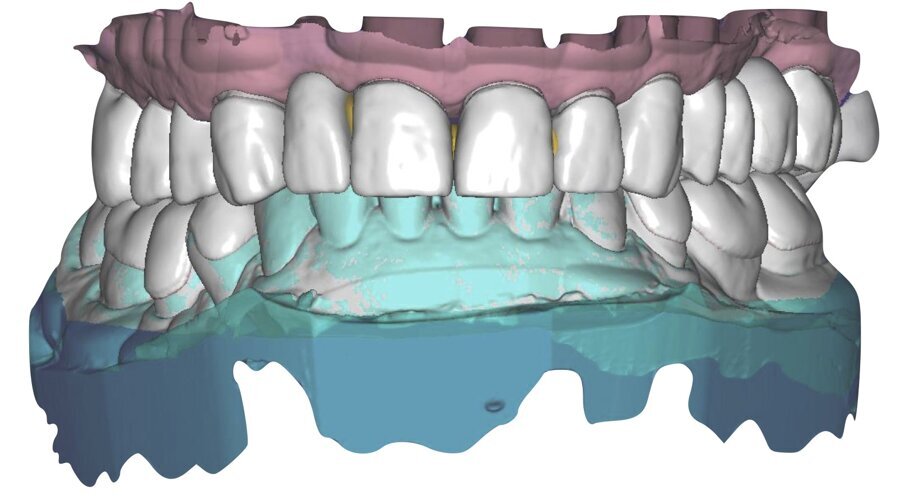

Ciò consente un miglioramento dei rapporti interarcata, un guadagno di spazio protesico in regioni premolari e molari, ed il mantenimento di uno spazio protesico conforme ad una corretta anatomia per i denti vitali da 1.3 a 2.3. Al paziente viene pertanto aggiornato il piano di trattamento e proposta la riabilitazione in TRP, con la previsione di overlays all’arcata inferiore per costruzione del nuovo piano occlusale. In posizione terapeutica sono modellati i coni delle centriche attive sui monconi sfilabili all’arcata inferiore, per la successiva individuazione al CAD con modulo articolatore del piano occlusale studiato. Questo rapporto articolare in TRP è ora scansito con scanner da laboratorio Xanos Evo Scan Compact (Fig. 24).

I modelli sono così importati in corretta posizione spaziale tramite il modulo exocad Virtual Articulator (Fig. 25). Non avendo a disposizione nel CAD l’analogo virtuale dell’articolatore Reference SL, viene impostato il sistema virtuale SAM, che usa lo stesso piano di riferimento axio-orbitale e geometria sovrapponibile al Reference SL. Per la programmazione virtuale dei parametri funzionali dell’articolatore si riesegue l’output dall’axiografia elettronica con Gamma Dental per SAM (Fig. 26). Si procede perciò ora con la modellazione CAD della ceratura mantenendo il riferimento dato dal piano occlusale individuato dai coni di centrica scansiti con l’articolatore (Fig. 27). L’articolatore virtuale consente una prima verifica dei rapporti occlusali tra gli elementi e un abbozzo di funzionalizzazione delle cuspidi con strumenti virtuali dinamici, che permette di arrivare ad un CAD design vicino alla morfologia ricercata (Figg. 28-33). Il modellato è ora fresato in cera Yeti Dental al CAM con fresatore VHF Cam5-S1 ed i denti in cera, tutti singolarmente sfilabili, sono posizionati sui modelli eseguiti con stampa 3D.